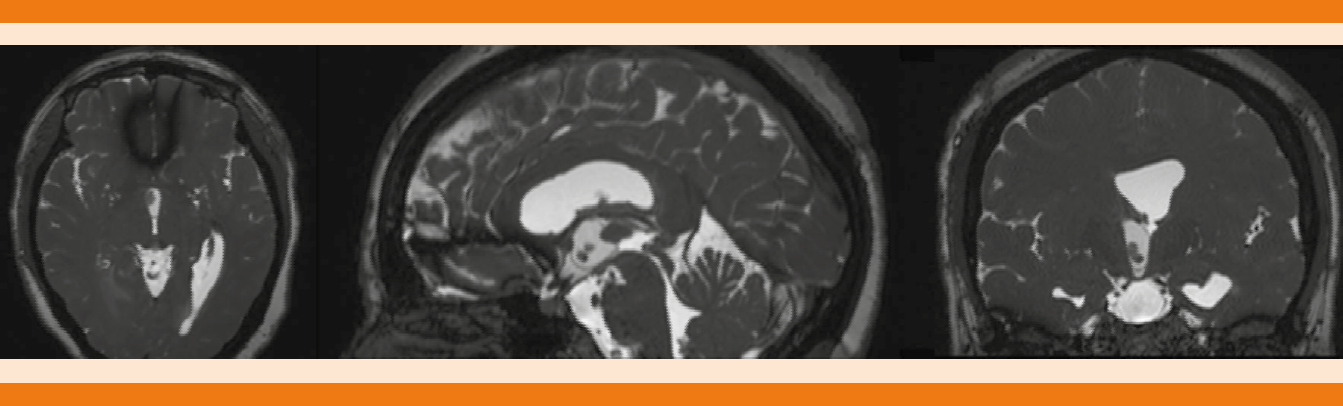

La tomografía de cráneo simple y con contraste evidenció hidrocefalia aguda no comunicante y edema cerebral. Se procedió a colocación de válvula de derivación ventrículo-peritoneal, sin complicaciones con control tomográfico posterior donde se observó válvula de derivación ventrículo-peritoneal en el asta anterior del ventrículo derecho. Los estudios de imagen se complementaron con una resonancia magnética de cráneo en secuencia FIESTA (Figura 1) donde ese observó un quiste intraventricular anterior a la masa intertalámica con nódulo en su interior (escólex) y pared delgada bien definida, con lo que se estableció el diagnóstico de neurocisticercosis intraventricular. La paciente se sometió a una neuroendoscopia para extracción del quiste (Figuras 2 y 3). El procedimiento se realizó sin complicaciones y durante el quinto día de hospitalización se inició tratamiento con albendazol a dosis de 15 mg/kg/día y esteroides. La paciente tuvo buena evolución clínica, con mejoría del estado de alerta, persistencia de inatención y con alteración de la memoria de trabajo; el resto de la exploración neurológica fue normal.

Figura 1 Resonancia magnética secuencia FIESTA que muestra un quiste intraventricular anterior a la masa intertalámica con escólex en su interior y una pared delgada bien definida.

En la neurocisticercosis ventricular, la TAC muestra lesiones hipodensas que causan hidrocefalia obstructiva asimétrica y los quistes dentro del ventrículo se observan isodensos con el líquido cefalorraquídeo y no pueden visualizarse directamente. El diagnóstico por imagen puede ser difícil, por lo que se utilizan secuencias especiales como FIESTA (fast-imaging employing steady-state adquisition), que tiene mayor resolución y cortes más delgados para ver las paredes de los quistes que pueden pasar inadvertidos en secuencias normales.1,3

El caso comunicado representa una localización poco común de la neurocisticercosis y una manifestación clínica poco frecuente. El abordaje diagnóstico requirió una serie de estudios de imagen para poder establecer la causa. La secuencia FIESTA fue esencial para el diagnóstico y el tratamiento definitivo fue mediante neuroendoscopia para la extracción del quiste intraventricular. La neurocisticercosis continúa siendo un problema de salud pública en las zonas endémicas como nuestro país; sin embargo, el acceso al tratamiento cisticida y el desarrollo de técnicas quirúrgicas mínimamente invasivas han mejorado el pronóstico de los pacientes.